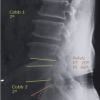

The table summarizes demographic and clinical characteristics. Of 50 patients, 66% are male, and 34% are female. Smoking prevalence is 28%. Diagnoses include 24% with DDD and 76% with disc herniation. Radiculopathy affects L4 (8%), L5 (60%), S1 (26%), and L5-S1 combined (6%), highlighting L5 as the most common site (Fig. 1).

Figure 1: Visual Analog Scale scores.